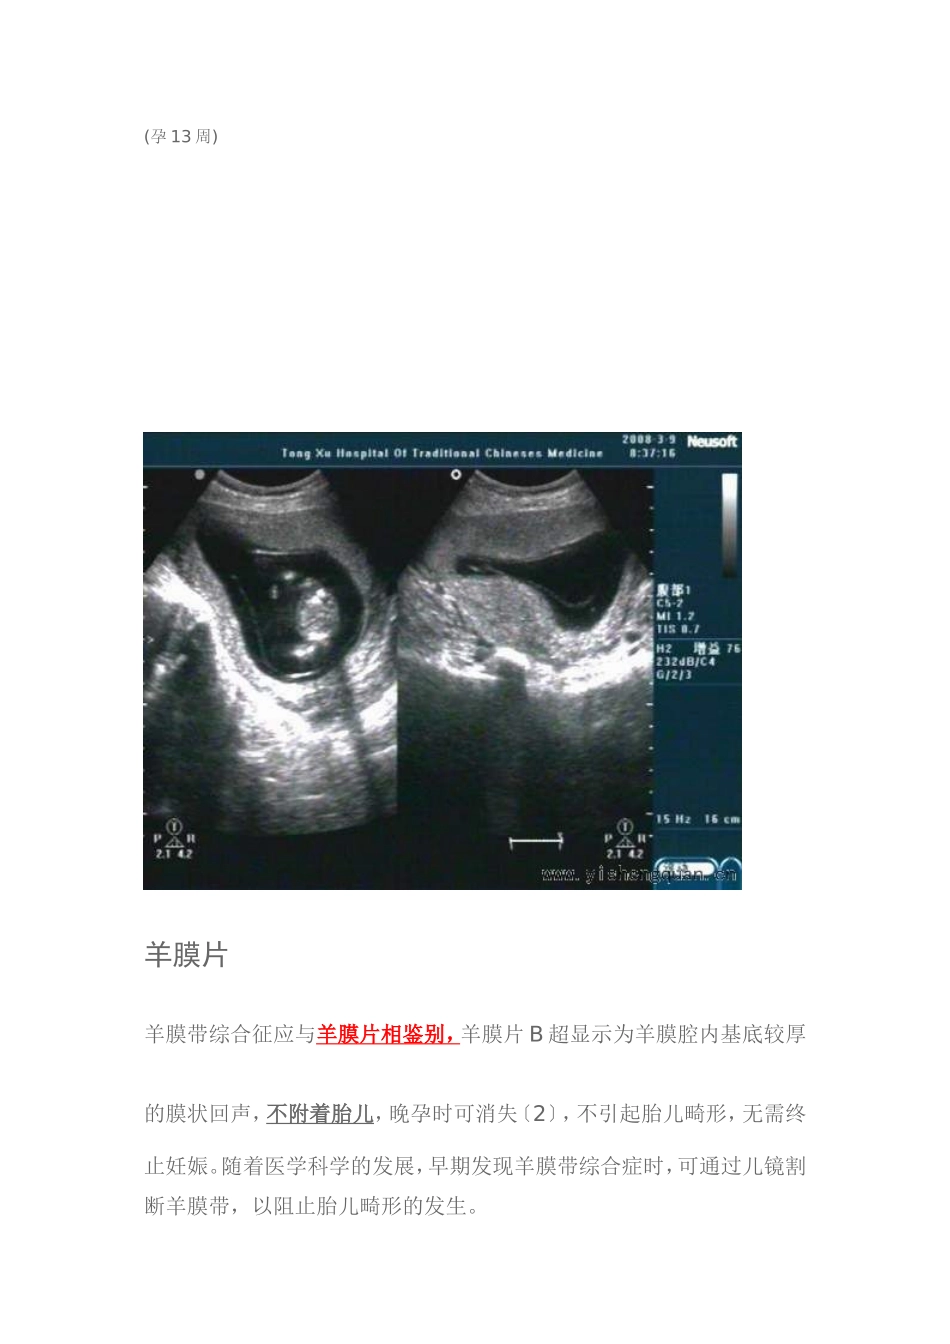

羊膜绒毛膜分离羊膜片轮状胎盘羊膜带综合征羊膜绒毛膜分离约在停经后22天,在内细胞团表层下有羊水积贮,形成羊膜囊。羊膜囊很快增大,在第6孕周时其直径约略小于2mm。第7孕周时则约3-5mm大小,外形可稍扁平。以后其形态可随孕囊形态及有无宫缩等情况而定。羊水系一种无色透明液体,在声像图上显示为液性暗区。羊膜菲薄,厚仅5层上皮而已,超声显示困难。在第10-16孕周间,应用实时超声仔细观察,特别是当子宫被振摇时,可以发现羊膜囊的部分羊膜的回声。应用TVS(阴超)法则羊膜显示更易,发现时间也更早(第8-9孕周)。羊膜囊与绒毛膜之间的空隙为胚外体腔。随着孕龄增长,羊膜囊越来越大,胚外体腔则越来越小。一般在每16孕周时羊膜囊可充满整个绒毛膜腔,羊膜与绒毛膜全部融合,胚外体腔消失,也有少数人胚外体腔在第16孕周后仍可存在,但通常不会迟于第20孕周。偶也有羊膜与绒毛膜互不融合,称为羊膜绒毛膜分离。一般认为此无重要临床意义。羊膜囊、胚外体腔等对超声诊断意义不大,其预后意义也尚不明-------摘自:超声医学第四版P1323(孕13周)羊膜片羊膜带综合征应与羊膜片相鉴别,羊膜片B超显示为羊膜腔内基底较厚的膜状回声,不附着胎儿,晚孕时可消失〔2〕,不引起胎儿畸形,无需终止妊娠。随着医学科学的发展,早期发现羊膜带综合症时,可通过儿镜割断羊膜带,以阻止胎儿畸形的发生。(此图为孕9月余,宫内膜状回声,胎儿未见明显异常)轮状胎盘典型的轮状胎盘,一般无临床意义.是胎盘的胎儿面中心内凹,周围环绕增厚的灰白色环,环是由于双折的羊膜和绒毛膜构成的,其间有退化的蜕膜及纤维.在环内,胎儿面为常见有外形,并附着于脐带上,可见到有大血管中断于环的边缘.卷起增厚的羊膜绒毛组织常合并胎盘出血和梗死.轮状胎盘分为完全型(形成一完整的胎盘组织环),与部分型(形成不完整的胎盘组织环)两类.部分型轮状胎盘不引起任何胎儿异常,而完全型轮状胎盘与胎盘早剥,早产,IUGR,胎儿畸形,围生儿死亡率增高有关.羊膜带综合征羊膜带综合征是Torpin提出的一种设想—羊膜早破〔1〕,羊水外流至羊膜囊外(胚外体腔),羊膜部分或全部回缩而形成羊膜带,胚胎或胎儿可突入胚外体腔与羊膜腔粘连,胎儿某一部分被羊膜包绕,使胎儿出现各种畸形。羊膜带综合征早期可有不对称性脑膨出,小眼球、面裂、腹壁缺如;晚期可造成各种肢体残缺,肢体缩窄,肢体截断,指、趾融合和畸形足等。上述3例胎儿骨髂及内脏结构均未见异常。由于羊膜带将胎儿颈部与宫腔壁相系,致使胎儿活动受限。羊膜带综合症也称为羊膜带破裂并发症。是一组不复发的,由羊膜粘连缠绕胎体不同部位而形成的一组畸形。病理上,羊膜带综合征造成的畸形有三大类:肢体畸形、颅裂面裂及腹壁缺损。它们包括肢体及指趾的狭窄环或截断、马蹄内翻足畸形、双侧肢体不对称和不定形的脑膨出、面部缺损、鼻异常、唇裂及腹裂等。由于缠绕的纤维带是随意的,出现的畸形可以是不相同的。严重时胎儿被羊膜带紧紧缠绕,固定在某种姿势,体位强直,出现脊柱异常弯曲、足畸形等等。诊断:本病超声首先发现的异常改变是胎儿畸形,尤其是脑膨出、腹裂最容易被观察到。脑膨出可以发生在任何部位,有腹裂者肠管多位于腹腔外。在肢体畸形中,仔细观察能发现双侧肢体不对称或存在狭窄环或截肢、截指趾。一旦声像图上显示条状羊膜带附着在畸形部位,羊膜带综合征的诊断便可成立。然而有时超声不易观察到羊膜带回声,其中有的是因为羊水过少,影响了超声对指趾及羊膜带的观察。根据此病的畸形特征,产前超声一般能作出诊断,并非必须显示羊膜带才能诊断。鉴别诊断:1.羊膜绒毛膜分离。孕16周以前未与绒毛膜融合的正常羊膜带可表现为线状强回声。2.双胎。双羊膜腔的双胎妊娠之间的隔膜。3.轮状胎盘突入羊膜腔内的部分较薄时,也可表现为膜状回声。4.不全纵隔子宫的纵隔较薄时。以上的隔样物都不与胎体相连羊膜带综合征相关知识---此内容转载于中国超声医师网先天性环状粘连带;先天性缩窄环综合征;蛛网综合征;羊膜索综合征;Sfreeter畸形概述:羊膜带综合征(amnioticbandsyndrome)的名称很多,如先天性环状粘连带蛛网综合征等,是...